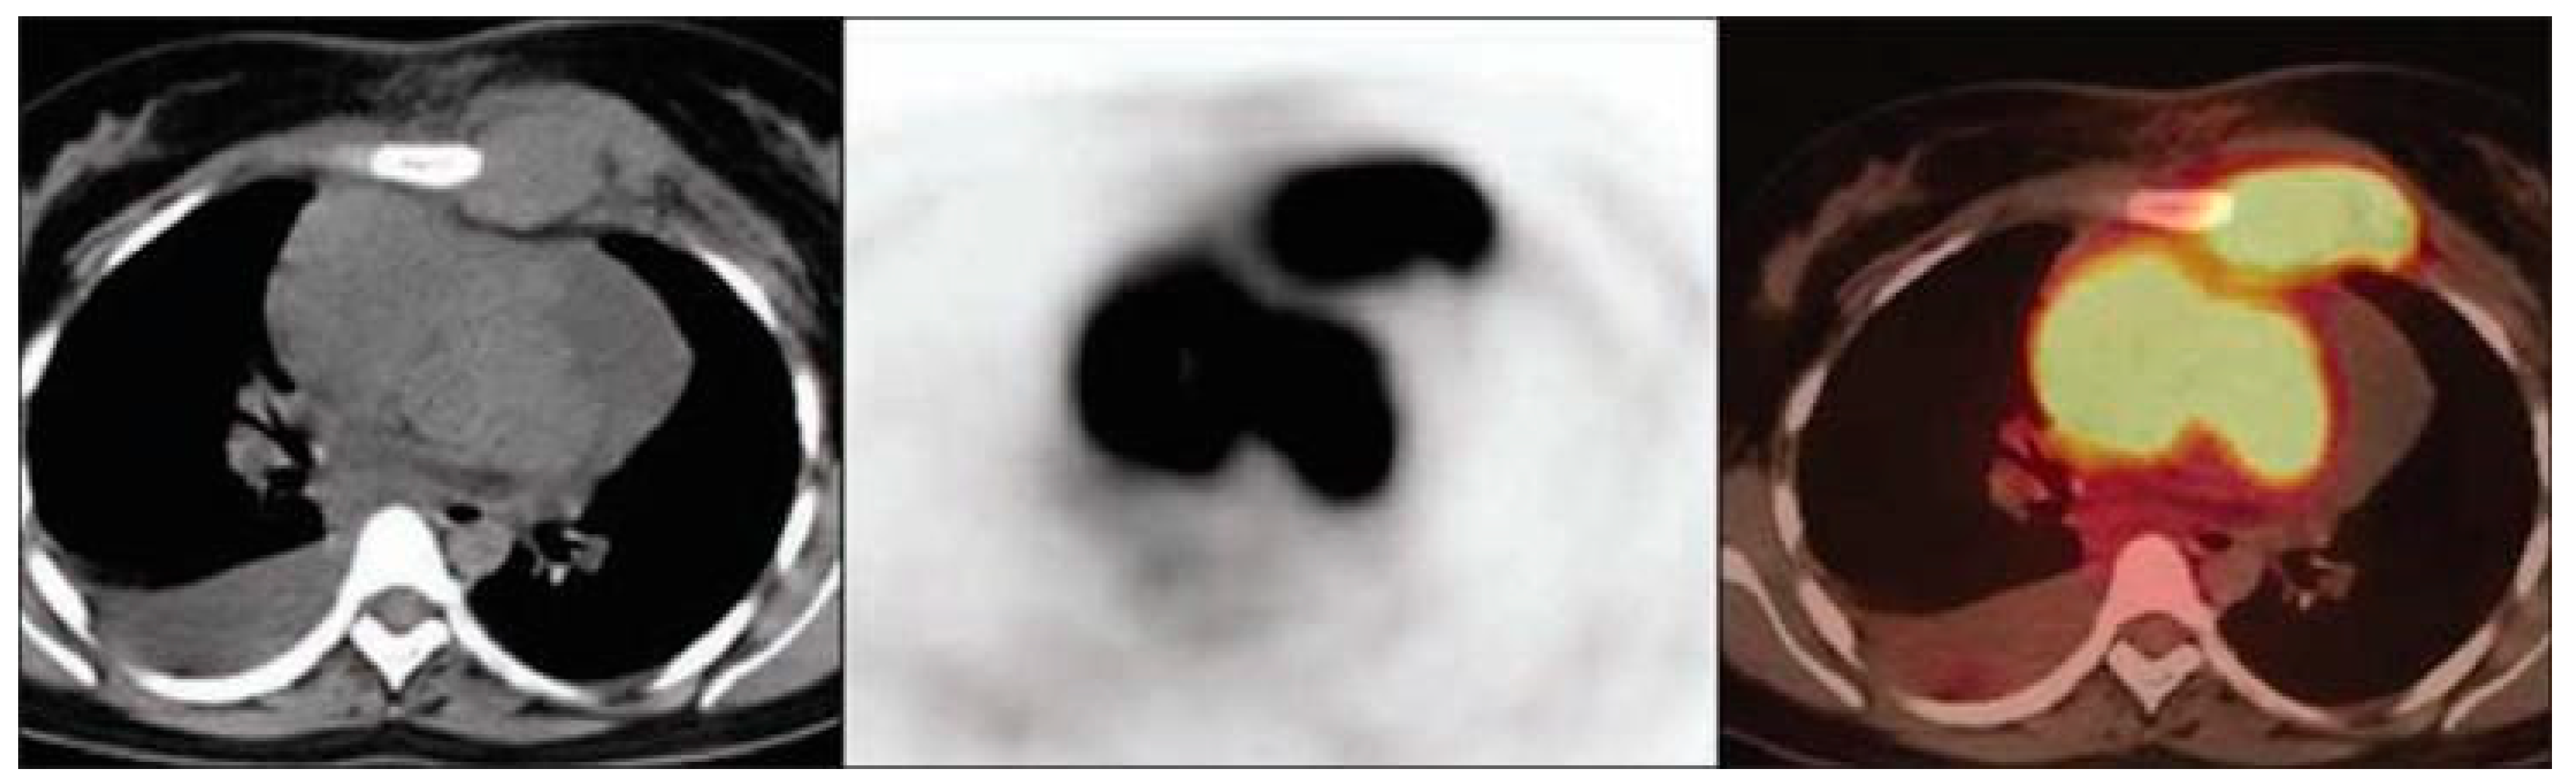

- Basu, S.; Alavi, A. Role of FDG-PET in the Clinical Management of Paraneoplastic Neurological Syndrome: Detection of the Underlying Malignancy and the Brain PET-MRI Correlates. Mol. Imaging Biol. 2008, 10, 131–137. [Google Scholar] [CrossRef]

- Scheid, R.; Lincke, T.; Voltz, R.; von Cramon, D.Y.; Sabri, O. Serial 18F-Fluoro-2-Deoxy-D-Glucose Positron Emission Tomography and Magnetic Resonance Imaging of Paraneoplastic Limbic Encephalitis. Arch. Neurol. 2004, 61, 1785–1789. [Google Scholar] [CrossRef] [PubMed]